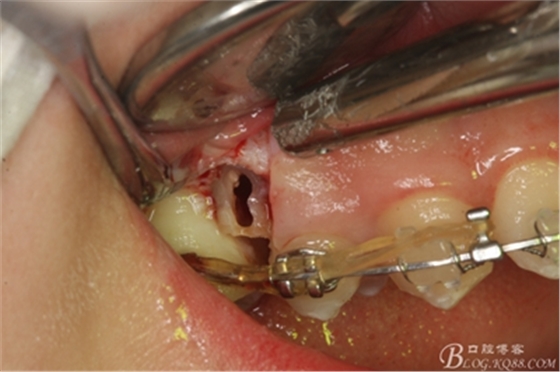

圖8.因16與14合面的間隙僅2mm左右,牙根無法合向脫位,如何考慮15牙根的脫位將是最大問題。高速手機去除牙間隙內(nèi)的覆蓋在15牙根表面的牙齦組織

圖10.去除牙齦組織后。露出15牙根斷面,合面無法脫位